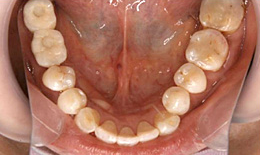

- 下顎

- インプラントを2本埋め込んで、セラミックスクラウンを被せた